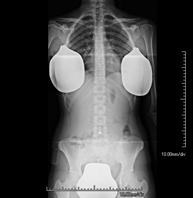

Tècnica que usa els raigs X a través de la qual s'obtenen imatges del sacre i del còccix per al seu estudi. Indicacions: traumatisme, dolor sacre o coccigi. - Telerradiologia columna

Tècnica que usa els raigs X a través de la qual s'obtenen imatges de tota la columna vertebral per al seu estudi, amb la valoració especialment de la presència d'escoliosi i dismetries pèlviques.

Tècnica que usa els raigs X a través de la qual s'obtenen imatges de tota la columna vertebral per al seu estudi, amb la valoració especialment de la presència d'escoliosi i dismetries pèlviques. - Telematria EEII (Extremitats Inferiors)